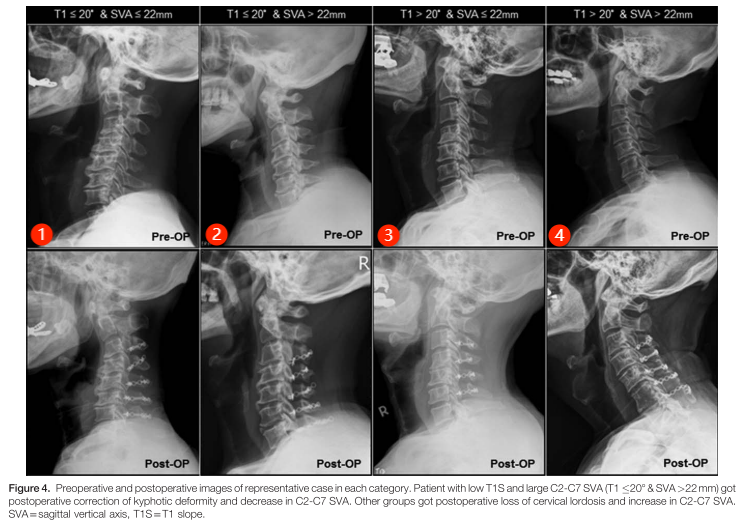

1、小CSVA,小T1 SLOPE,术后颈椎前凸轻度丢失;

2、大CSVA,小T1 SLOPE,术后颈椎前凸恢复;

3、小CSVA,大T1 SLOPE,术后颈椎前凸轻度丢失;

4、大CSVA,大T1 SLOPE,术后颈椎前凸明显丢失。

以T1 SLOPE 代表整体平衡,以CSVA代表颈椎平衡,但目前对于术中脊柱整体矢状位情况与LAMP术后颈椎前凸角的丢失缺乏明确的研究。